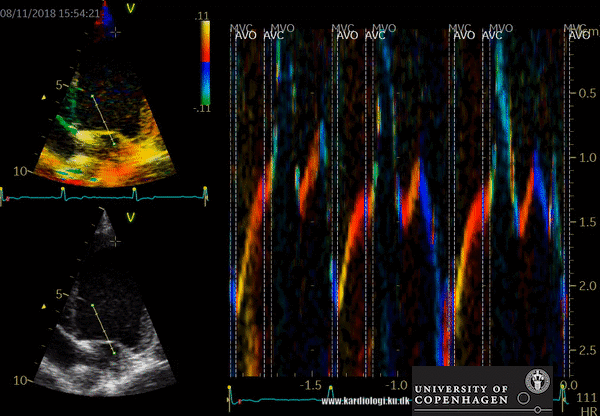

Color TDI derived tissue velocity curves from the mitral annulus (septum and lateral). The curves show velocities towards the probe (positive velocity) in systole, and away from the probe (negative velocities) in diastole. The cardiac cycle is presented by three main waveforms - one positive systolic wave (S´, as the heart base, moves towards the apex in systole) and 2 negative diastolic peaks (E´ represent a passive filling curve and A´ represent the atrial contraction curve, as heart base ascends away from the apex).

A color TVI image obtained from an apical 4CH view sampling the septal and lateral mitral annulus. Note the positive curve after closure of the aortic valve representing a post systolic shortening (PSS = myocardial shortening after end-systole) of the left ventricle. PSS can be caused by delayed electrical activation of the myocardium often associated with ischemia.